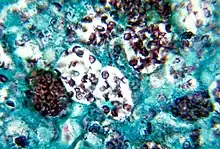

| Histoplasma capsulatum. Methenamine silver stain showing histopathologic changes in histoplasmosis | |

Histopathology of Histoplasma capsulatum, H&E stain, showing organisms surrounded by halos, in a granuloma of epithelioid histiocytes. Histopathology of Histoplasma capsulatum, GMS stain, showing narrow budding yeast

Histopathology of Histoplasma capsulatum, GMS stain, showing narrow budding yeast Histoplasma capsulatum var. duboisii, methenamine silver stain